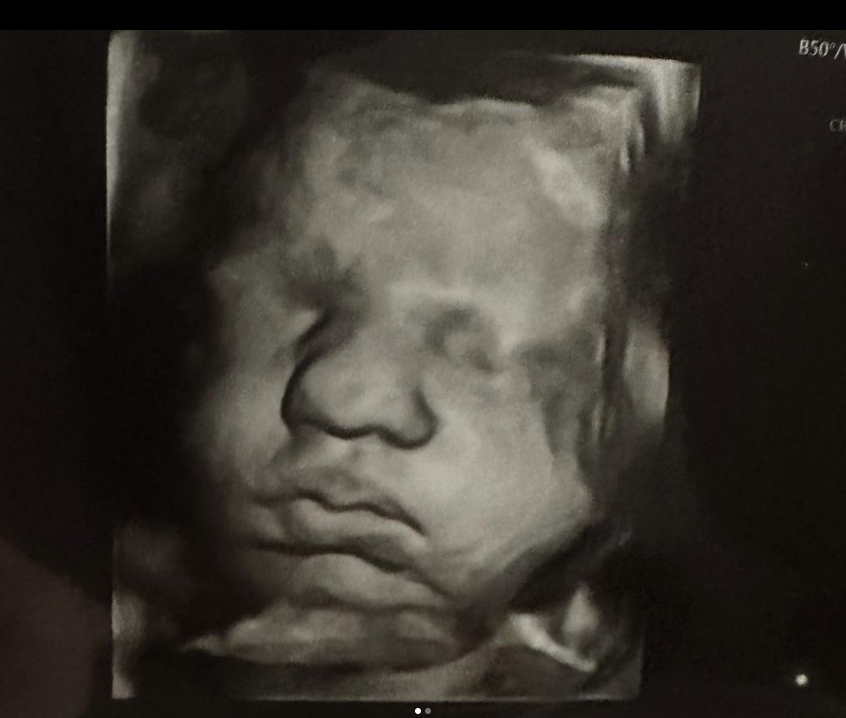

Screenshot des zur Verfügung gestellten Ultraschallbildes ©doubleuhatchlings, Kelsey Hatcher